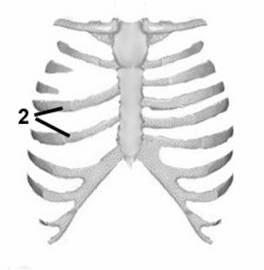

Рис. 3. Схема операции при синдроме Поланда.

1 - гипоплазированные 3 и 4 ребра; 2 - перемещенные 5 и 6 ребра.

Таким образом костный дефект закрываем за счет увеличения межреберных промежутков в нижнем отделе грудной клетки.